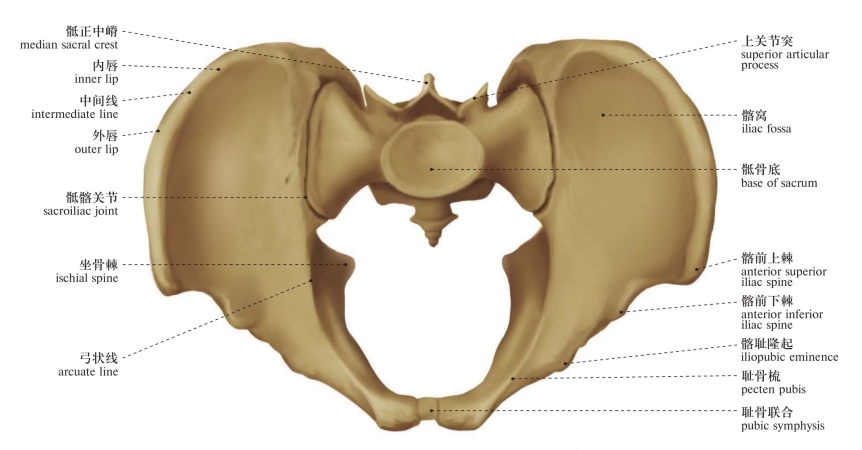

图35 骨盆(后面观)

Pelvis (posterior aspect)